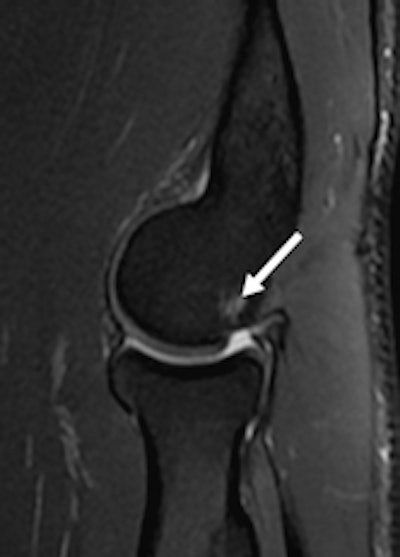

A 30-year-old male judo athlete with valgus stress and hyperextension injury of elbow. Top: Coronal proton density-weighted fat-saturated MRI shows full-thickness tear (white arrow) of proximal humeral attachment of anterior bundle of ulnar collateral ligament (UCL) and edema (black arrow) within surrounding muscle fibers. Below: Axial proton density-weighted fat-saturated MRI shows UCL posterior bundle disruption (long white arrow), with fluid surrounding ulnar nerve (short white arrow). However, ulnar nerve was contiguous on sequential images, with no transection. High-grade tear of flexor carpi ulnaris (black arrow) also was seen. Bottom: Axial proton density-weighted fat-saturated MRI shows high-grade tear of flexor digitorum superficialis (long arrow) and fluid surrounding median nerve (short arrow). All images reprinted with permission from the American Journal of Roentgenology.